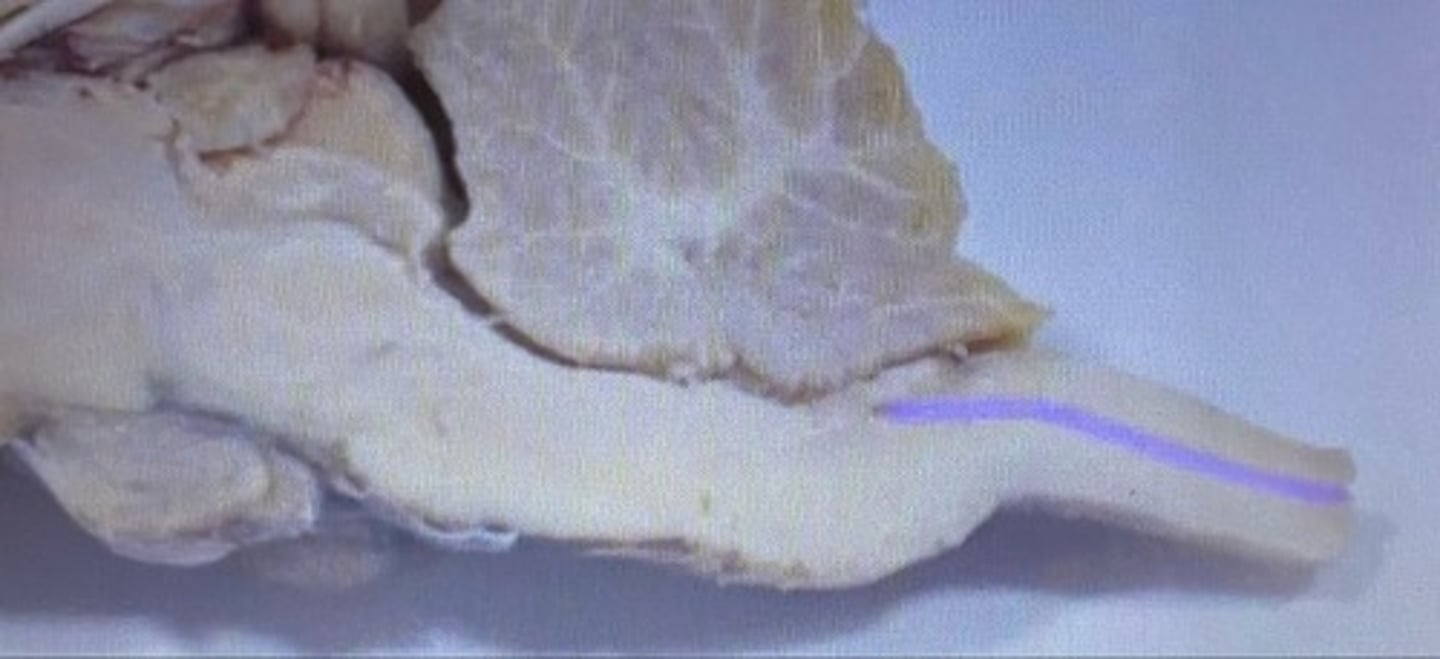

Spinal Cord

Sheep Central Canal